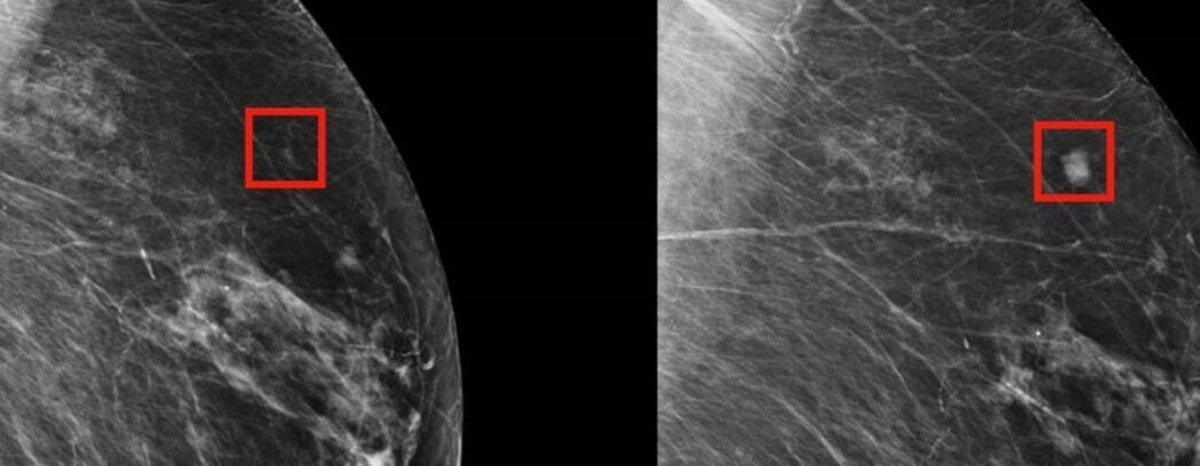

ماموگرافی استاندارد در تشخیص سرطانهای کوچک سینه در زنان با الگوی سینه دارای چربی بالا (تراکم سینه) بسیار موثر است. سرطان سینه در ماموگرافی سفید و بافت چربی سیاه است. این کنتراست رنگی تشخیص سرطانهای کوچک سینه را نسبتا آسان میکند. با این حال وضعیت مذکور در بانوان با سینههای متراکم برعکس است. بافت متراکم پستان در ماموگرافی سفید است که تشخیص سرطانهای کوچک و سفید پستان را دشوارتر میسازد. به همین علت تشخیص سرطان سینه کوچک در یک سینه متراکم با چالش یافتن آدم برفی در طوفان برف مقایسه شده است.

زنان جوان بیشتر از زنان مسن سینههای متراکم دارند. یک مطالعه معتبر نشان داد که ۷۴ درصد از بانوان ۴۰-۴۹ ساله دارای سینههای متراکم هستند. مطالعه مهم دیگری که از طریق وب سایت کتابخانه ملی پزشکی آمریکا در اختیار علاقهمندان قرار گرفته است، نشان داده که ۹۸ درصد از سرطانهای سینه در زنان با سینههای متراکم طی غربالگری ماموگرافی شناسایی نشدند. علاوه بر این، تراکم سینه یک عامل خطر قابل ملاحظه برای ابتلا به سرطان سینه است و زنان با سینههای متراکم در معرض خطر بیشتری برای ابتلا به سرطانهای تهاجمی پستان هستند.